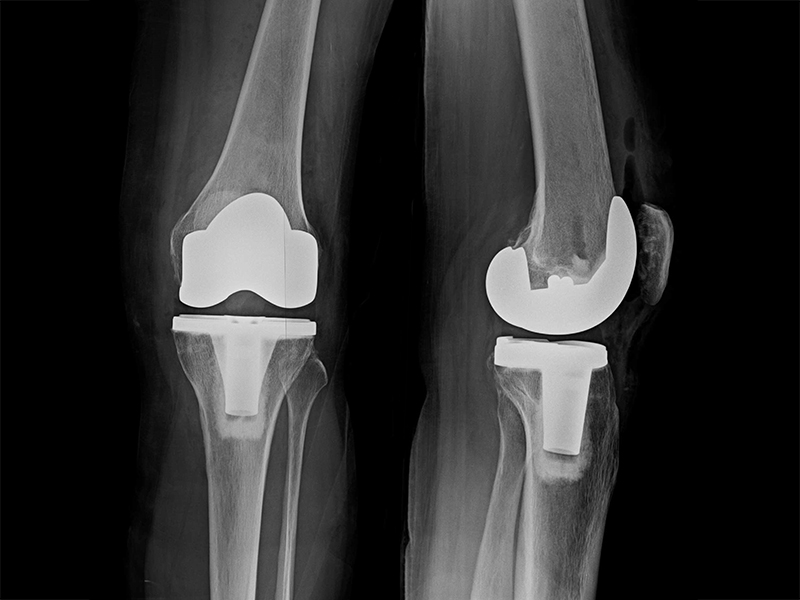

傳統全膝關節置換

更多